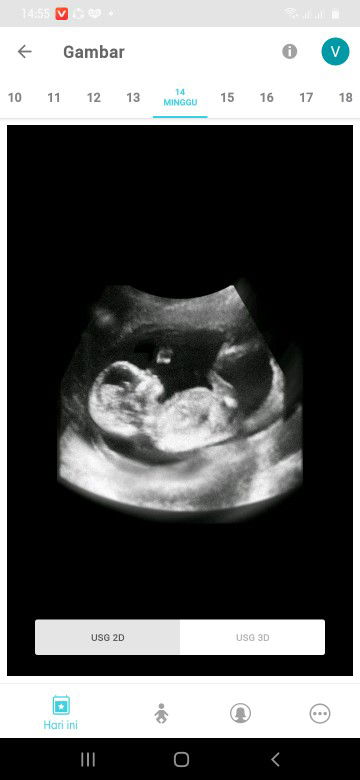

Assalamualaikum Sy hamil usia 7w Mingggu kmrn sy usg di bidan katanya uk kantong nya 1,89cm dan msh blm ada janin, apakah normal? Kl kata bidan nya sih normal bun Tp sy trauma akan janin tdk berkembang yg prnh sy alami 2th yg lalu, wkt itu usia 7w tp kantong kehamilan msh cm 10mm

normal Bunda saya juga 7week masih kantung 2,13 Cm dan Alhamdulillah skrg udah jalan 21 minggu tetap pikiran positif ya bunda

SM Bun aku jg baru kliatan kantong'y aja,usia 7mnggu tp aku jg tkut dokter bilng tkut ga berkmbng nunggu 2 Minggu LG untuk USG..

saya dulu 7w ukuran kantungnya 3cm bun dan belum ada janinnya, sampai sekarang belum berani usg lagi 😁

kalau aku sih ukuran 7 wek udah ada janinya udah ada djjnya juga